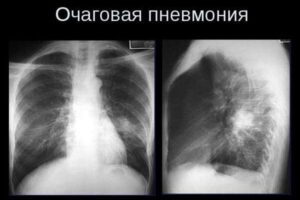

Что такое очаговая (бронхиальная) пневмония у ребенка

Статистика заболеваемости и смертности от пневмонии шокирует. Ежегодно от пневмонии умирает до 1,5 миллиона детей, что больше, чем от всех инфекций, вместе взятых (туберкулез, пневмония, корь, малярия и др.). Пневмония также является причиной смерти каждого шестого ребенка в возрасте до 5 лет. В этой статье мы рассмотрим причины, симптомы и лечение очаговой пневмонии у детей. …